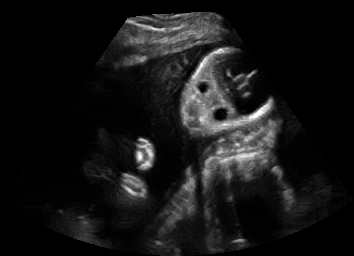

US simulation. We used a ray-tracing framework to render B-mode images from a geometric fetal model, by simulating a convex probe placed at multiple locations and orientations on the abdominal surface, with imaging settings listed in Tab 1. At each location, simply rasterizing a cross-section through the triangulated anatomical surfaces at the ultrasound center imaging plane provided corresponding semantic maps. Fig. 3 shows example B-mode images with corresponding semantic maps. A total of simulated frames were resized to and randomly split into training-validation-test sets by 80-10-10%.

In Fig. 3 we show that only learning an auxiliary seg-to-real translation, i.e. CUT+S, cannot guide the network to learn the semantics of simulated images.

CUT+SC with the loss term largely reduces hallucinated image content, although it still fails to generate fine anatomical details. With the multi-domain conditional generator and additional losses of ConPres, translated images preserve content and feature a realistic appearance. Training without leads to training instability.

Comparison to state-of-the-art. As seen qualitatively from the examples in Fig. 3, our method substantially outperforms the alternatives in terms of content preservation, while translating realistic US appearance. CycleGAN, SASAN, and CUT hallucinate inexistent tissue regions fail to generate fine anatomical structures, e.g. the ribs. StarGAN fails to generate faithful ultrasound speckle appearance, which leads to highly unrealistic images. Our method ConPres preserves anatomical structures, while enhancing the images with a realistic appearance. It further faithfully preserves acoustic shadows, even without explicit enforcement. However, as seen from the last column, the refraction artefact appears artificial in the images translated by all the methods. Note that although the imaging field-of-view (FoV) and probe opening in the simulation is significantly different from the real in-vivo images (Fig. 2) used for training, our ConPres maintains the input FoV closely compared to previous state-of-the-art. The results in Tab 2 quantitatively confirm the superiority of our method. Note that SSIM and FID/KID are used to measure translation performance from two different and sometimes competing aspects, with the former metric for quantifying structure preservation and the latter metrics for image realism.